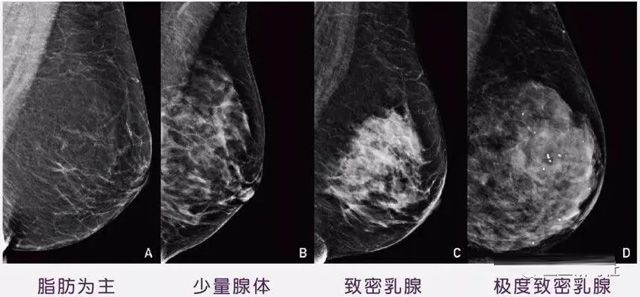

女性乳腺的自我檢查,特別是注意有小結(jié)節(jié),腫塊,乳頭有液體滲出情況,需要通過乳腺DR,X光線,磁共振等影像技術(shù)檢查。胸的大小跟乳腺癌沒多大關(guān)系,乳腺的密度大發(fā)病率高一些,胸小脂肪少致密性大。更容易乳腺癌。這個(gè)還不能通過自我檢查來確認(rèn)。致密乳腺組織看上去是白色或淺灰色需要通過乳腺X射線檢查。